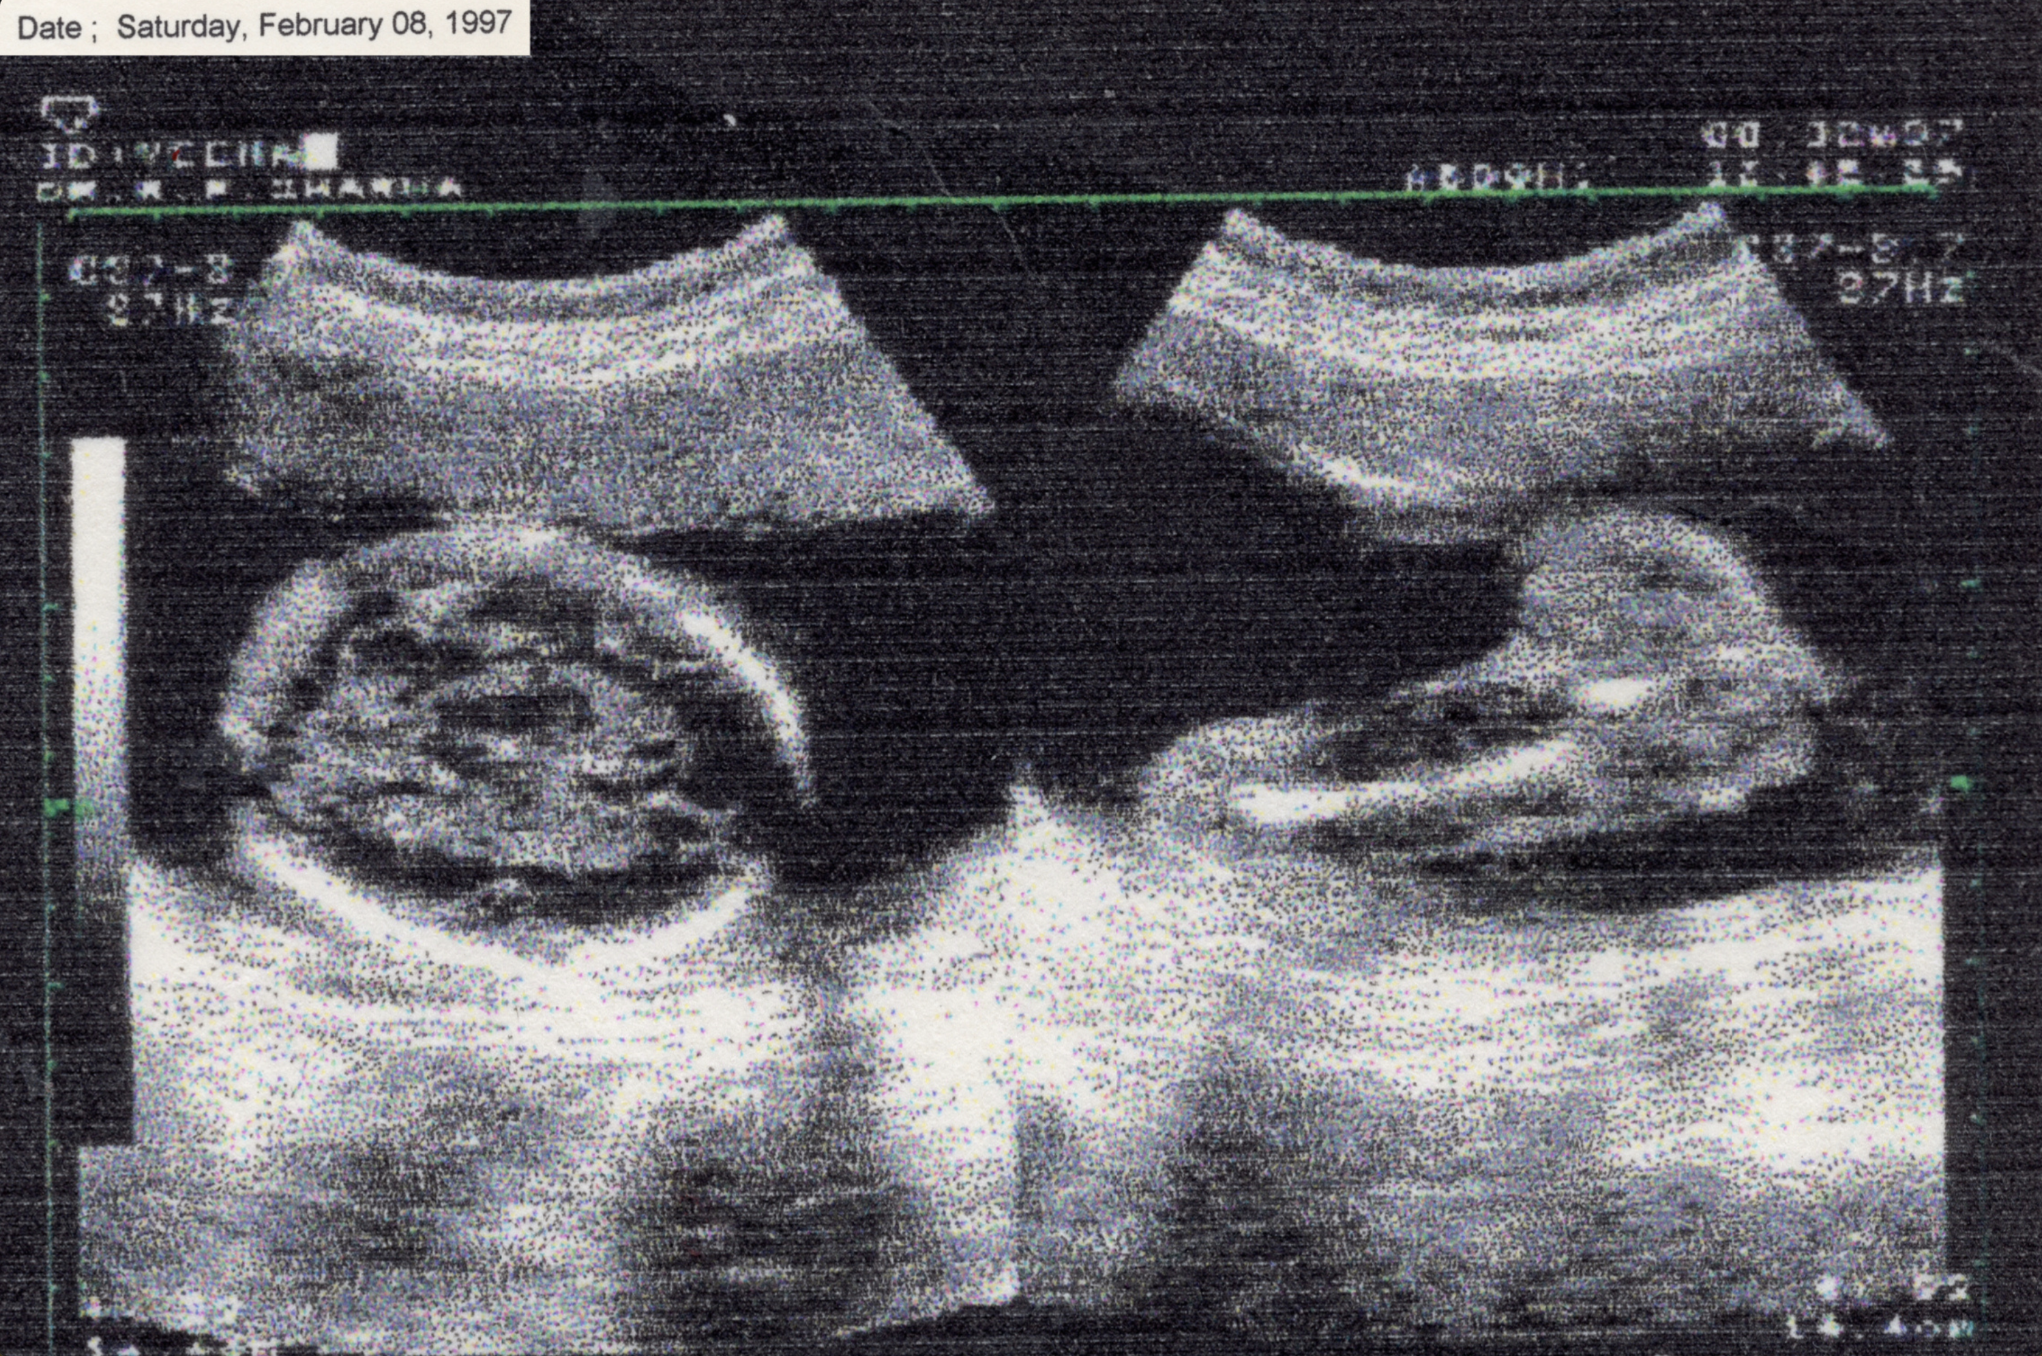

In July 2019, I was diagnosed with Guillain-Barré Syndrome, a rare neurological condition that quickly brings you to complete paralysis. Eventually, I regained movement, but I did not recover the same way inside. My body healed, yet I remained estranged from it. This disconnection between my body and soul continues to shape how I live. In ‘There Is No Other Home’ I explore Still-Life, text, sculpture and mixed media experiments to address the Non-Linearity of Healing, and depict healing as a loop. Using staged photography I reflect on how trauma rewires both memory and body. The images move between absence and presence, rupture and repair, exploring the tension of detachment and reattachment to one’s own body. ‘There Is No Other Home’emerges from the space between chaos and understanding. My body often feels like it carries its own memory. My hands loose grip, I stumble more often, and I freeze at things others take for granted, like driving. I return to fragments of memory, my mother’s CT scan when she was carrying me and my twin sister, a childhood photograph, not as evidence of illness but as traces of fragility, endurance, and survival. Working with hands became central. Sensations of tingling in my fingers was the first sign of my illness, so I sculpted and cast hands as a way to confront the absence of movement.